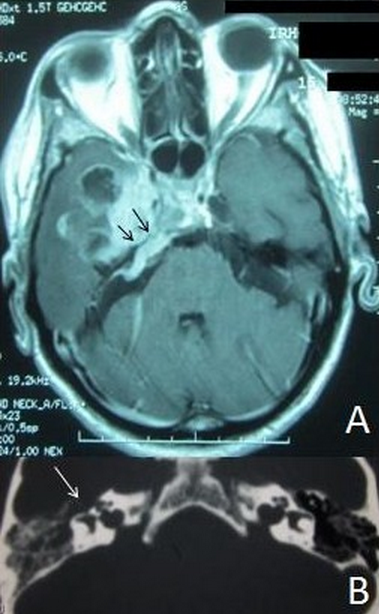

Il s'agit d'un patient de 48 ans suivi depuis 4 ans au service d'ORL pour une otite séromuqueuese droite pour laquelle il a était mis plusieurs fois sous traitement médical à base de corticoïdes et d'antibiotiques locaux et systémiques. A la lumière d'un bilan radiologique ce patient a été déclaré porteur d'une métastase temporale d'un cancer primitif pulmonaire- comprimant la trompe d'eustache, lysant l'os temporal et responsable d'une fuite du liquide cérébrospinal dans le conduit auditif externe (prise à tord comme étant une otomastoïdite). Ce diagnostique de métastase a été confirmé par une biopsie stéréotaxique. Le patient est décédé 4 mois après sa première séance de radiothérapie conventionnelle. Le cancer du poumon est le premier cancer prometteur de métastases cérébrales, la localisation temporale de ces métastases est pourvoyeuse de crises comitiales avec ou sans déficit neurologique. A notre connaissance, il n'a pas été déjà décrit qu'une otomastoïdite peut révélée ce type de lésion qui reste de mauvais pronostique.